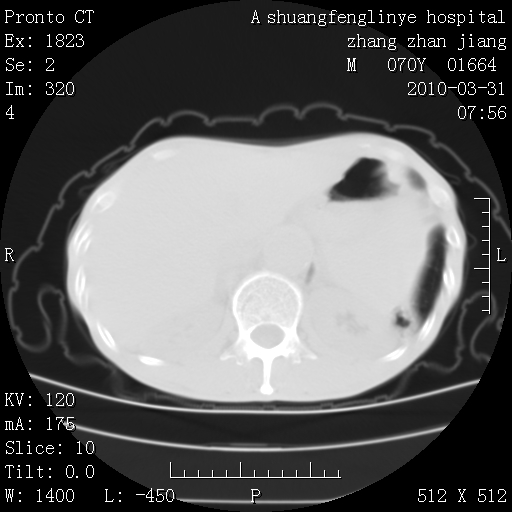

双上肺继发型tb并左上空洞形成,主动脉冠脉钙化。

1)两肺上叶继发性肺结核并左肺上叶空洞形成。2)冠状动脉及主动脉钙化。